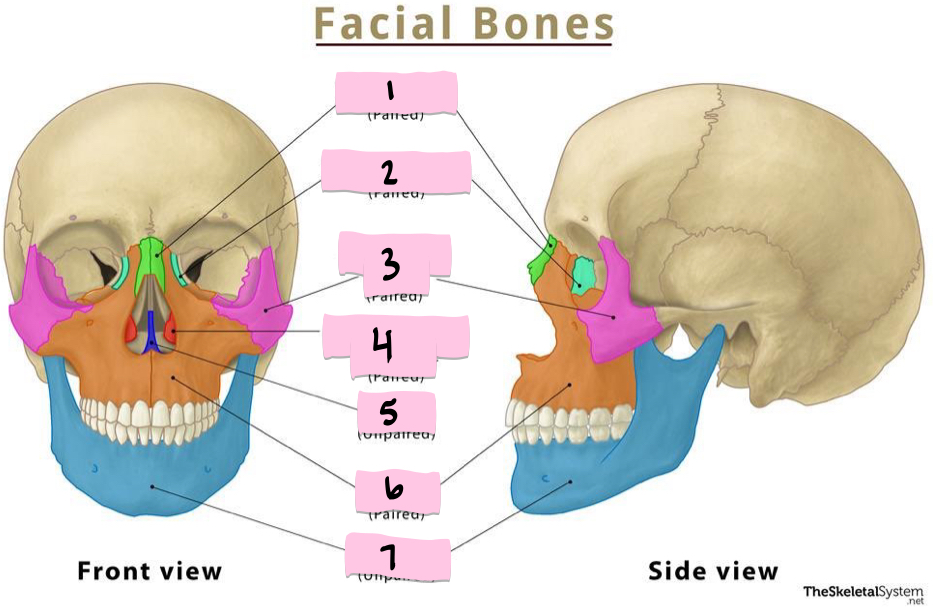

What is 1 pointing to?

Nasal bone

What is 2 pointing to?

Lacrimal bone

What is 3 pointing to?

Zygomatic bone

What is 4 pointing to?

Inferior nasal conchae

What is 5 pointing to?

Vomer

What is 6 pointing to?

Maxilla

What is 7 pointing to?

Mandible